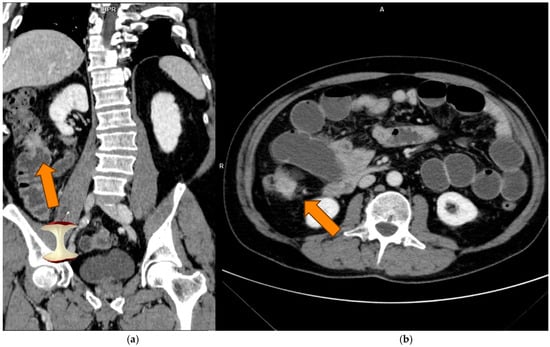

Prediction of Microsatellite Instability in Colorectal Cancer Using Two Internally Validated Radiomic Models

by Antonio Galluzzo, Ginevra Danti, Linda Calistri, Diletta Cozzi, Daniele Lavacchi, Daniele Rossini, Lorenzo Antonuzzo, Sebastiano Paolucci, Francesca Castiglione, Luca Messerini, Fabio Cianchi and Vittorio Miele

Objectives: To develop two different radiomic models based on preoperative contrast-enhanced computed tomography (PP CT) to predict microsatellite instability (MSI) in patients with colorectal cancer (CRC) before surgery. Methods: PP CT scans of 115 CC patients were segmented using 3DSlicer (v5.6.1). Model I [...] Read more.

Objectives: To develop two different radiomic models based on preoperative contrast-enhanced computed tomography (PP CT) to predict microsatellite instability (MSI) in patients with colorectal cancer (CRC) before surgery. Methods: PP CT scans of 115 CC patients were segmented using 3DSlicer (v5.6.1). Model I included images from three different scanners (GE, Siemens, Philips), while Model II used only one scanner (GE). For Model I, 80 patients were used for training and 35 for internal validation; for Model II, 46 and 24 patients were used, respectively. Data on sex, age, tumour location, and MSI genomic status were collected. A total of 107 radiomic features (RFs) were extracted, and 30 and 35 RFs were identified as relevant for Models I and II, respectively, using the t-test or Mann–Whitney test (p < 0.05). The most robust RFs were selected using the LASSO regression method. Both models were internally validated. Results: Model I, based on 2 RFs and 1 clinical feature (LOCATION) achieved an AUC of 0.76 (95% CI: 0.65–0.87) in the training cohort and 0.74 (95% CI: 0.56–0.92) in the validation cohort. Model II, based on 3 RFs, achieved an AUC of 0.85 (95% CI: 0.73–0.96) in the training cohort and 0.72 (95% CI: 0.50–0.94) in the validation cohort. Conclusions: Both radiomic models showed good performance in distinguishing between MSI and non-MSI tumours, potentially reducing the need for invasive histological testing and improving treatment timing. Despite achieving a higher AUC, Model II showed signs of overfitting when compared to Model I, which incorporated two RFs and one clinical feature (LOCATION). Radiomics may function as a non-invasive preoperative screening tool to inform decisions regarding MSI testing and treatment. Building radiomic models on larger, more diverse datasets is preferable to enhance generalizability and reduce overfitting. Full article

(This article belongs to the Section Abdominal Imaging)